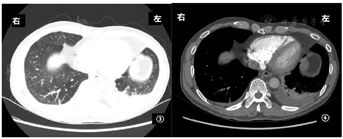

血气分析示:pH值7.394,PaO2:71.2 mmHg,PaCO2:40.1 mmHg,HCO3-:24 mmol/L;血白细胞:13.40×109/L,以淋巴细胞增加为主[中性粒细胞5.5×109/L(0.410),淋巴细胞6.5×109/L(0.485)],血红蛋白137 g/L,血小板288×109/L。肝肾功能、二便常规、凝血功能及D-二聚体未见异常;乳酸脱氢酶(LDH)164.3 U/L;红细胞沉降率97 mm/1 h,C反应蛋白0.87 mg/dL;其余感染相关抽血指标(降钙素原、血EB病毒DNA、T-Spot、G试验、GM试验均阴性;痰细菌学相关指标(细菌、真菌涂片及培养,抗酸杆菌涂片及结核杆菌DNA)均阴性;血肿瘤指标提示:CA125增高(77.5 U/mL),其余神经元特异性烯醇化酶(NSE)、癌胚抗原、CA153、TPS、FPSA均阴性;抗核抗体增高,效价为1∶100(核颗粒型);抗核抗体谱抗组蛋白抗体弱阳性,余项均阴性;ASO、类风湿因子、血管炎指标均阴性;血IgM 12.2 g/L、补体C3:0.735 g/L、补体C4:0.114g/L,IgG、IgA均正常范围内;免疫固定电泳显示免疫球蛋白Kappa弱阳性、IgM弱阳性,IgG、IgA及Lamda均阴性;血清蛋白电泳:白蛋白为47.8%、γ-球蛋白为28.1%;2020年12月1日胸部CT(图1,图2)提示双肺多发实性小结节影(大小3~5 mm),双侧胸腔少量积液,纵隔多发增大淋巴结,肺动脉造影未见异常。

因患者拒绝有创检查,遂先予抗感染(左氧氟沙星0.5 qd静脉滴注)7 d。至2020年12月8日复查胸部CT(图5,图6)提示病情进展,双肺多发实性小结节影较前增多,两下肺渗出及胸腔积液增多。